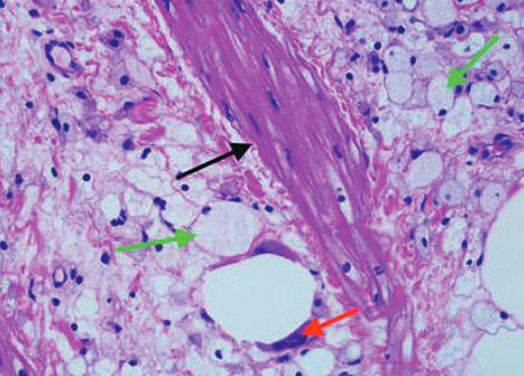

Фотографии и изображения, связанные с симптомами первичного склерозирующего холангита